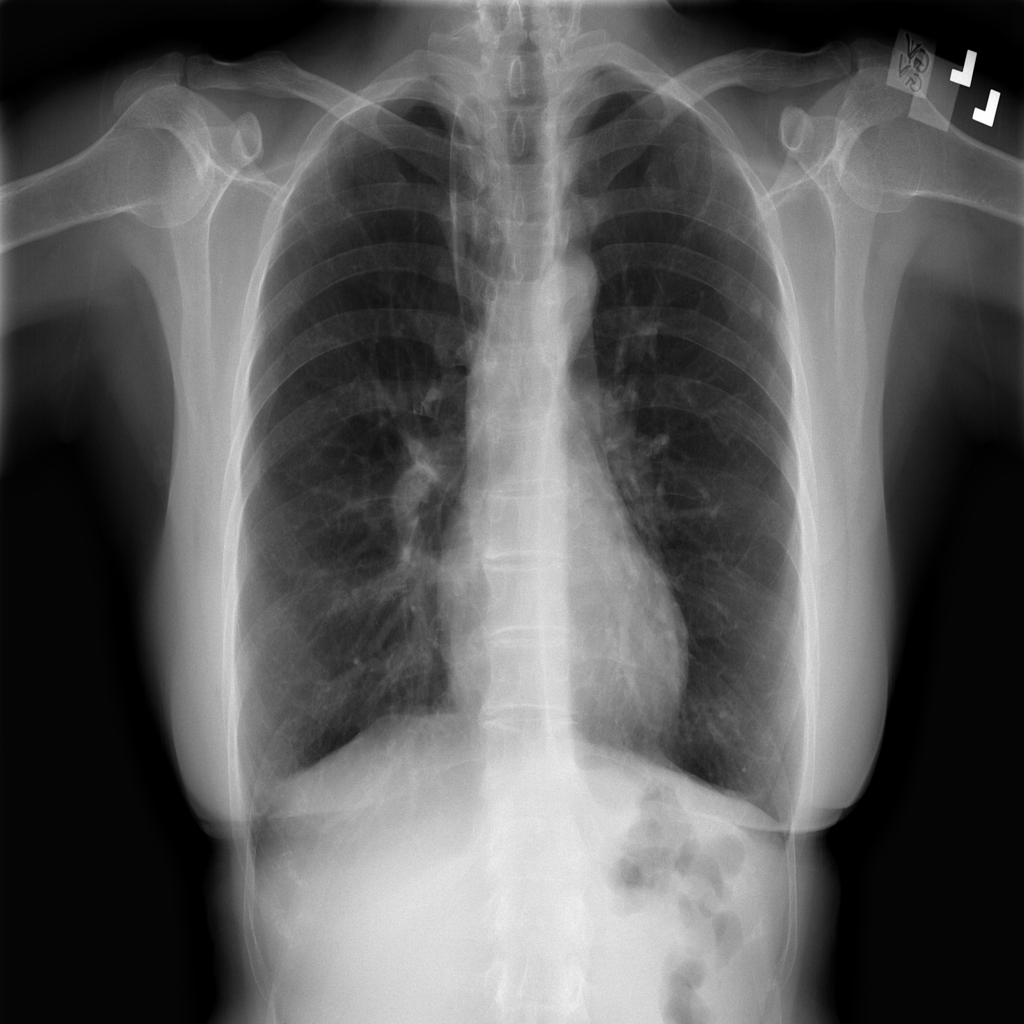

Showing up to 90 reference images for Nodule.

PAT-FB8F · IMG-000Nodule

PAT-FB8F · IMG-000

PA